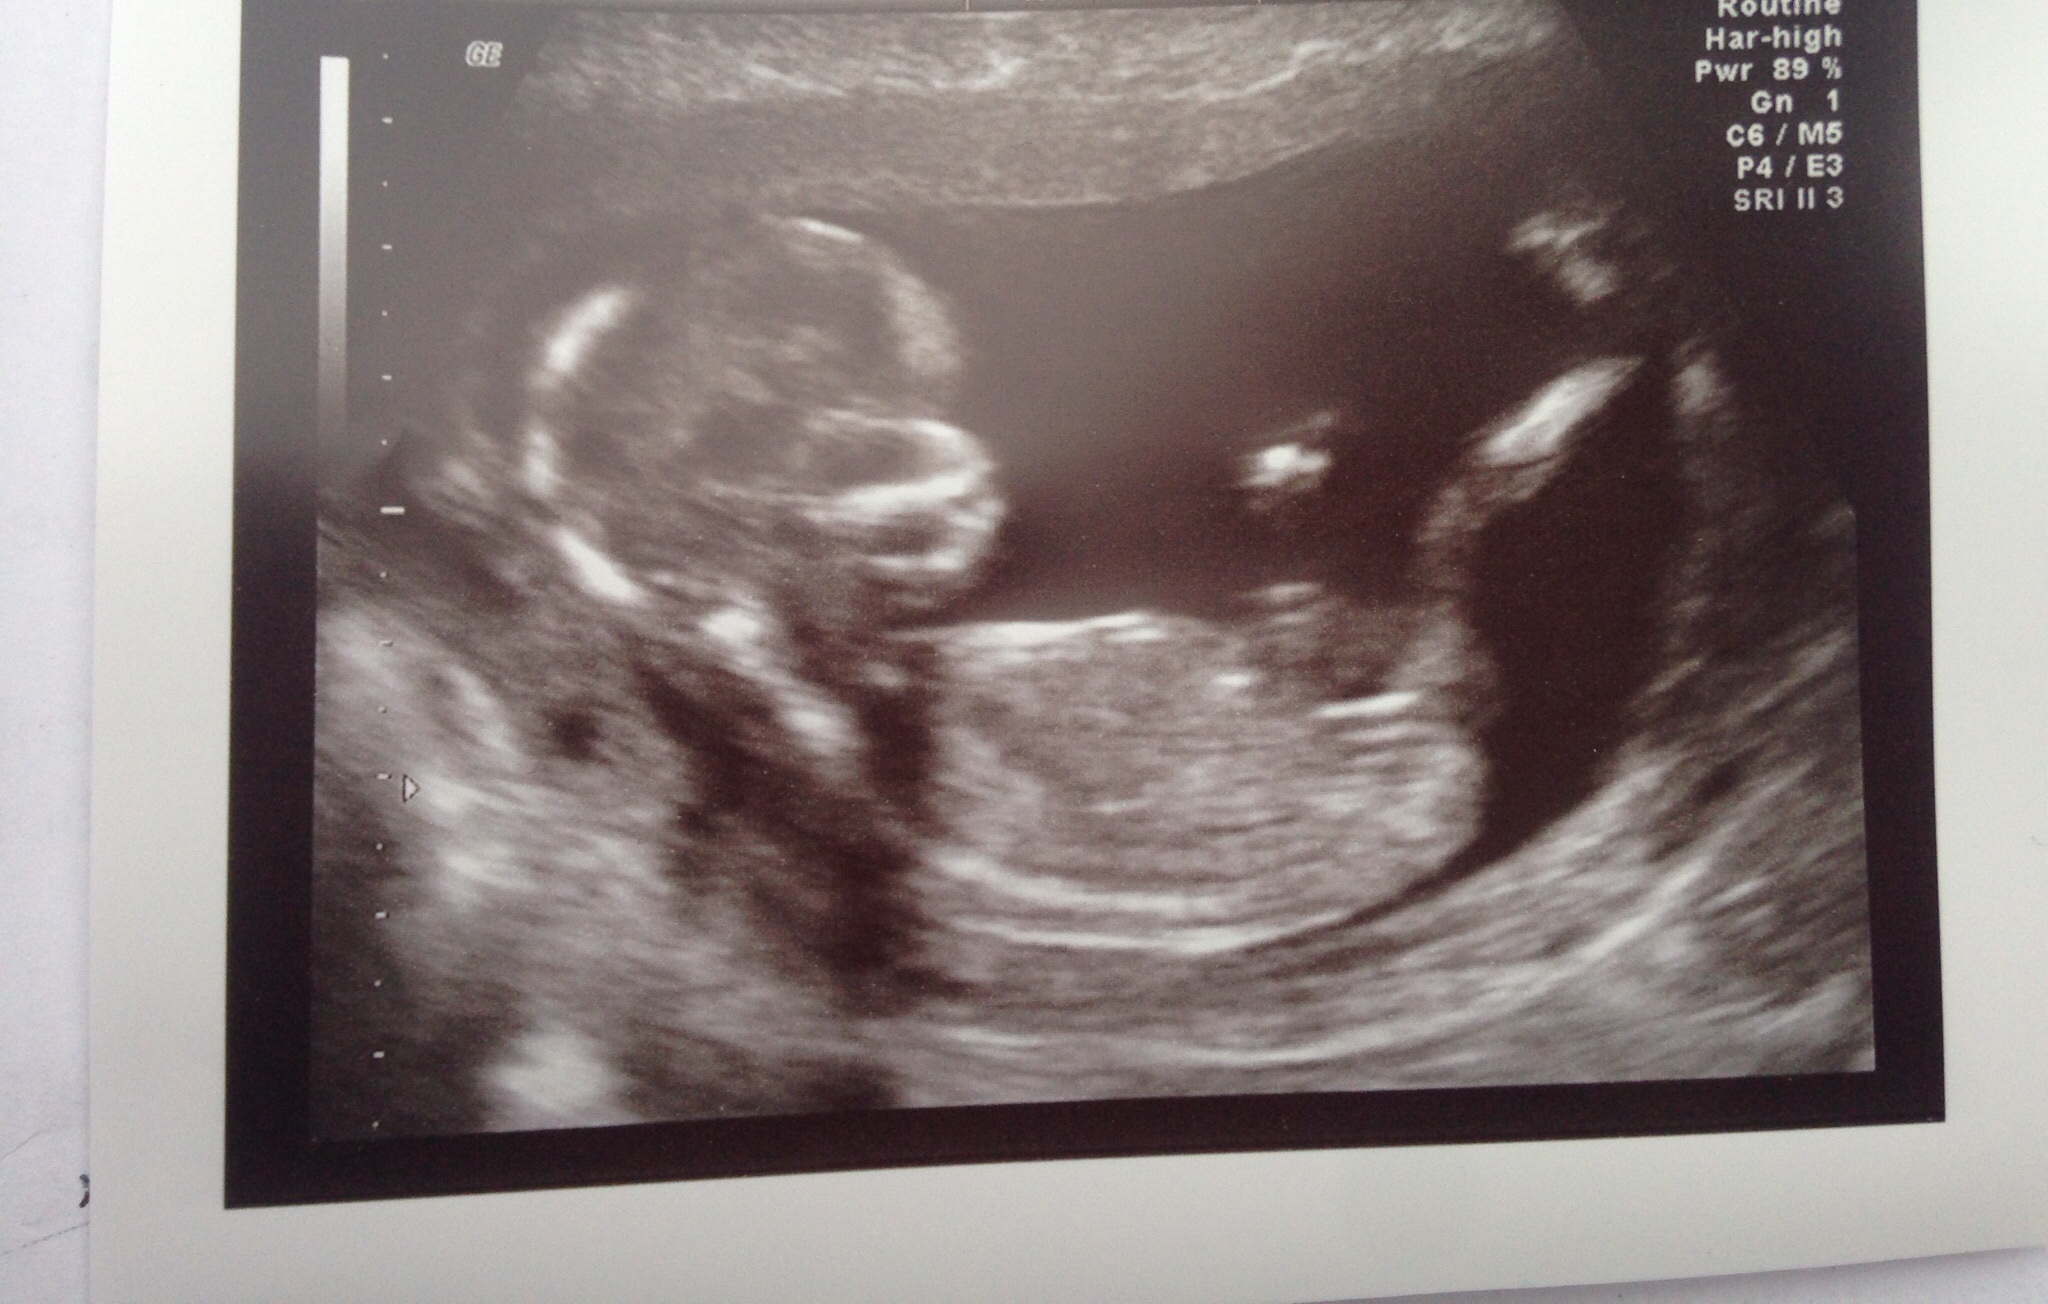

Hey, I'm new on here. Here's my 14week scan, any ideas on what baby could be?

Maaaaaaybe girly?? But I am not sure at all.

Also maybe girl. But no clear nub.

girl lean but not clear.

Maybe girl, but hard to see the nub.